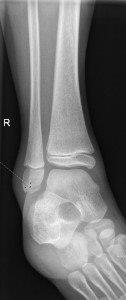

Avulsion fracture of distal fibula

Placeholder image

• No formal follow up required.